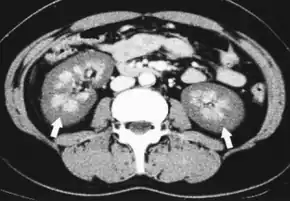

While the only diagnostic "gold standard" mechanism of diagnosis en vivo is via kidney biopsy, the clinical conditions and blood clotting disorder often associated with this disease may make it impractical in a clinical setting. Alternatively, it is diagnosed clinically, or at autopsy, with some authors suggesting diagnosis by contrast enhanced CT.[19]